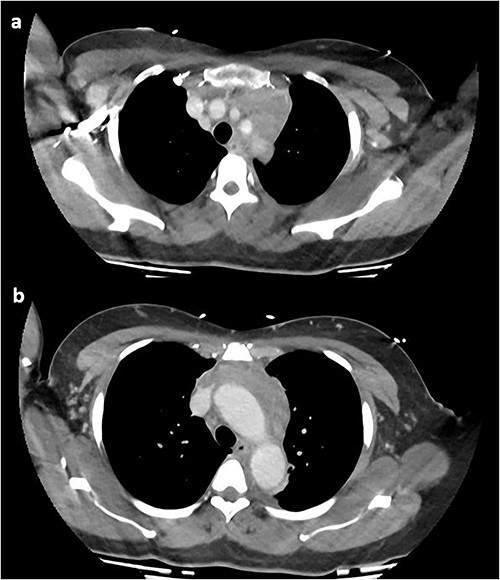

On repeat review of the CTPA, imaging was deemed atypical for acute aortic syndrome. A CT aortogram with delayed phase was performed, which demonstrated a 66-mm upper anterior mediastinal soft tissue density compressing the left brachiocephalic vein, as seen in Fig. 2.

CT chest with contrast demonstrating anterior mediastinal soft tissue density in the (a) upper chest and (b) lower chest.